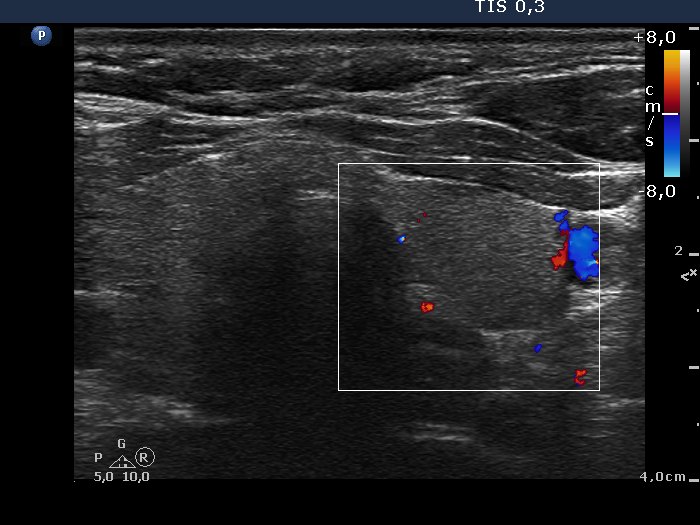

Consecutively operated patients with autoimmune thyroid disease - case 57 (conp 003) (ultrasonographic picture 6)

Left lobe, transverse view, color Doppler mode. The vascularization is decreased.